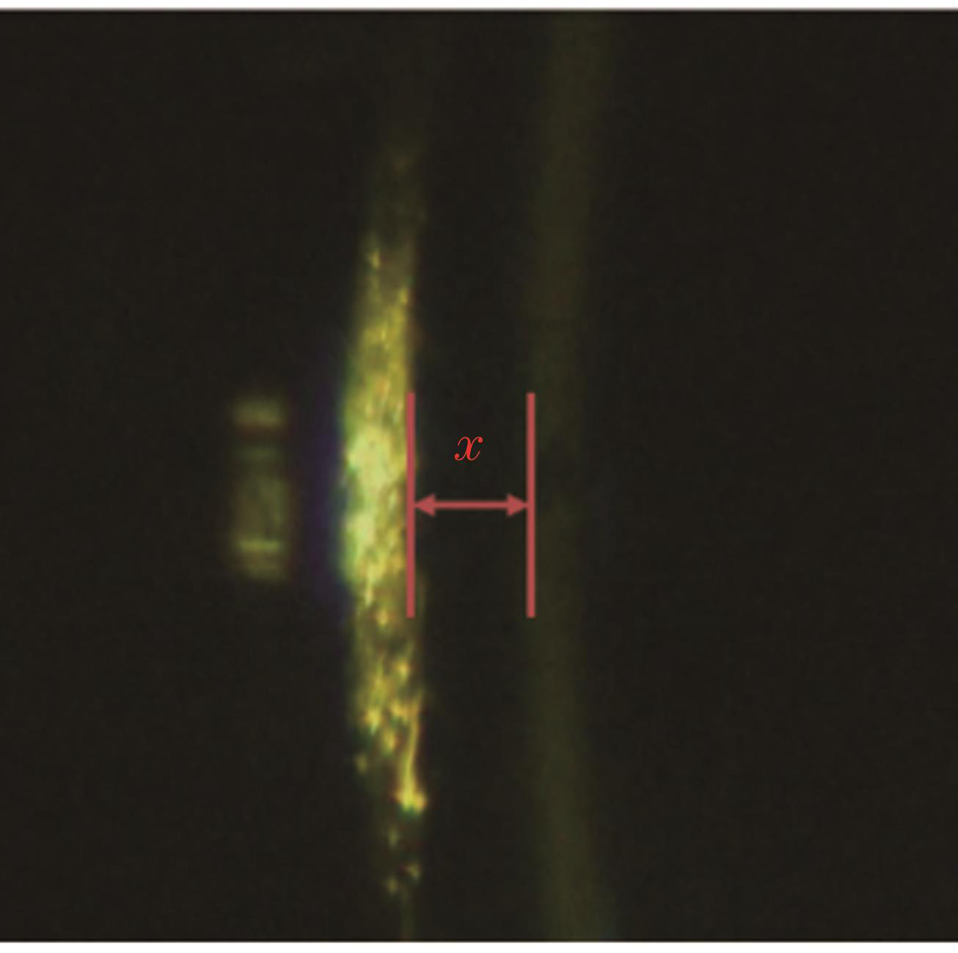

LED光源S1发出的光经光阑I1、柱面镜L1形成裂隙光,裂隙光经眼睛的晶体和角膜反射后进入L7、L8及L10~L13组成的物方远心光路并成像在CCD2上,如

式中:ACD为前房深度;R为角膜曲率半径;x为角膜与晶体反射像的间距;n为角膜折射率,一般取1.336;ω为裂隙灯入射角。

图 2. 角膜和晶体反射后所成的像及距离x测量

Fig. 2. Image formed by reflection of cornea and lens and distance x measurement